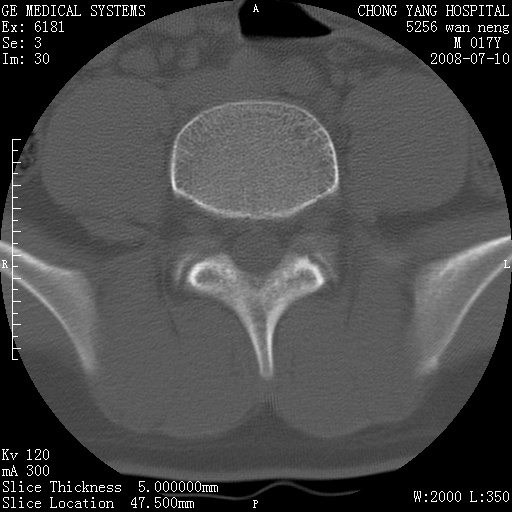

腰3、4椎弓崩裂

腰3、4椎弓不连

支持:腰3、4椎弓峡部崩裂。

腰3、4椎弓峡部不连

支持:腰3、4椎弓峡部崩解。

腰3、4,如受过外伤则为陈旧骨折,否则为骨质不连

图片漂亮,目前也只能看到腰3、4骨质不连

腰3、4椎弓峡部裂。

腰3、4椎弓峡部裂。支持

重建图像见多个椎弓峡部不连(不足为据),平扫未见异常。

支持腰3、4椎弓峡部崩裂。